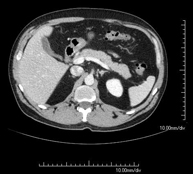

- Abdominal aorta CT angiography

A non-invasive diagnostic test that involves studying the abdominal aorta by obtaining high-definition anatomical images using CT (computed tomography) equipment and iodinated contrast. With the aid of workstations specialised for arterial studies, the image quality supports 2D and 3D reconstructions. It is indicated in patients with vascular disease (atherosclerosis), aortic aneurysms, abdominal pain of possible vascular origin, pre-surgical studies of lesions adjacent to the abdominal aorta as a vascular ‘map’, etc. Information obtained non-invasively is indispensable for patients requiring percutaneous or surgical processing. In patients who only require tracking of vascular lesions, this technique is the non-invasive technique of choice, together with MRI angiography.

- Renal artery CT angiography

A non-invasive diagnostic test that involves studying the renal arteries by obtaining high-definition anatomical images using CT (computed tomography) equipment and iodinated contrast. With the aid of workstations specialised for arterial studies, the image quality supports 2D and 3D reconstructions. This test is recommended, for example, in patients suffering from refractory hypertension that does not respond to processing, in patients with kidney damage in order to obtain a pre-surgical ‘vascular’ map, etc.

- Aortoiliac CT angiography

A non-invasive diagnostic test that involves examining the iliac arteries and abdominal aorta, obtaining high-definition anatomical images using CT (computed tomography) equipment and iodinated contrast dye. With the aid of workstations specialised for arterial studies, the image quality supports 2D and 3D reconstructions. This test is particularly recommended as a pre-surgical study (vascular map) prior to percutaneous or surgical interventions on the abdominal aorta, as a complementary study in patients with lower limb ischaemia, etc.